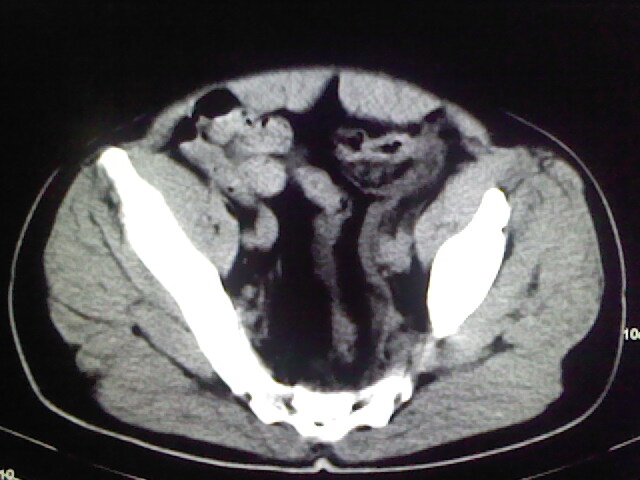

以下是引用zsl6918在2009-2-7 7:29:00的发言:[br]请提供介入的方式方法,肾及输尿管改变考虑与介入损伤有关,漏了,尿液外渗。

以下是引用余辉在2009-2-7 8:27:00的发言:[br]可能是硬化剂烧穿囊壁进入肾盂输尿管了,尿漏。不除外介入或碎石术后合并感染[br]患者术后怀疑结石,接着就碎石了?就怀疑没有确诊吗?碎石用的什么方法?气压弹道还是体外超声?如果这样的话责任人都难找

以下是引用随光逐影在2009-2-7 8:46:00的发言:[br]支持3楼意见。[br]另:不排除左肾及肾周感染可能。